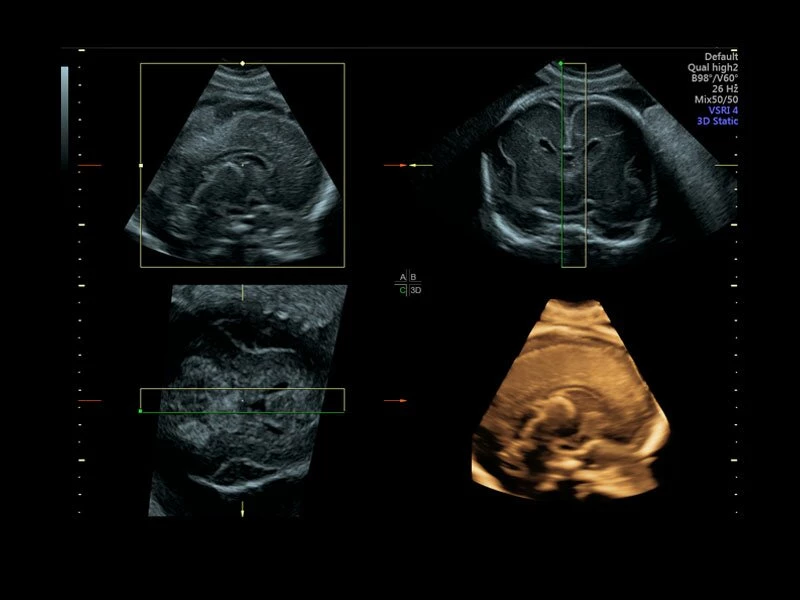

Voluson E10 – премиум класс среди ультразвуковых диагностических аппаратов для акушерских, гинекологических и объемных исследований. Аналогов системе Voluson E10 на рынке не представлено. УЗИ аппарат Voluson E10 обладает возможностью подключения электронного матричного датчика с количеством элементов не менее 8000.

Система обеспечивает инновационную четкость при работе. Новая платформа Radiance System Architecture системы разработана для превосходной визуализации как в стандартных режимах, так и при 3D/4D-визуализации.

Четкие и подробные изображения

В медицинском учреждении, которое работает в условиях высокой нагрузки, значение имеет каждая минута. У врача нет времени подолгу корректировать параметры настройки, чтобы добиться наилучшей детализации изображения. Инновационная архитектура УЗИ аппарата Voluson E10 избавляет вас от лишних хлопот, — вы сразу получаете безукоризненную картинку. Вам не придется тратить лишнее время и силы: качество визуализации безупречно в любом режиме — от двумерных изображений до новейших 3D/4D технологий.

Современные клинические приложения и высокое качество изображений позволяют использовать Voluson E10 для наблюдения за ходом беременности максимально эффективно. С помощью этого аппарата можно проводить любые исследования, как рутинные, так и комплексные, выявляя проблемы на ранних стадиях и принимая своевременные меры.

Объемное сканирование Voluson — 3D/4D вашей мечты

Объемное УЗИ на Voluson E10 — это не просто потрясающе красивая картинка, это ценный инструмент получения дополнительной информации при обследовании женщин.

Voluson E10 поддерживает инновационные технологии формирования изображений — HDlive Silhouette и HDlive Flow, которые позволяют увидеть мельчайшие детали. Алгоритм SonoRenderlive упрощает рабочий процесс и дает возможность реконструировать изображение поверхностей, определяя область перехода между тканью и жидкостью.

Инновационная технология визуализации HDlive обеспечивает получение реалистических изображений за счет эффекта объемного зрения, повышая достоверность клинической оценки. Теперь режим HDlive дополняют две новые функции:

- Технология HDlive Silhouette — задает разный уровень прозрачности, помогая выявлять контуры внутренних структур и точнее оценивать состояние плода в первом триместре.